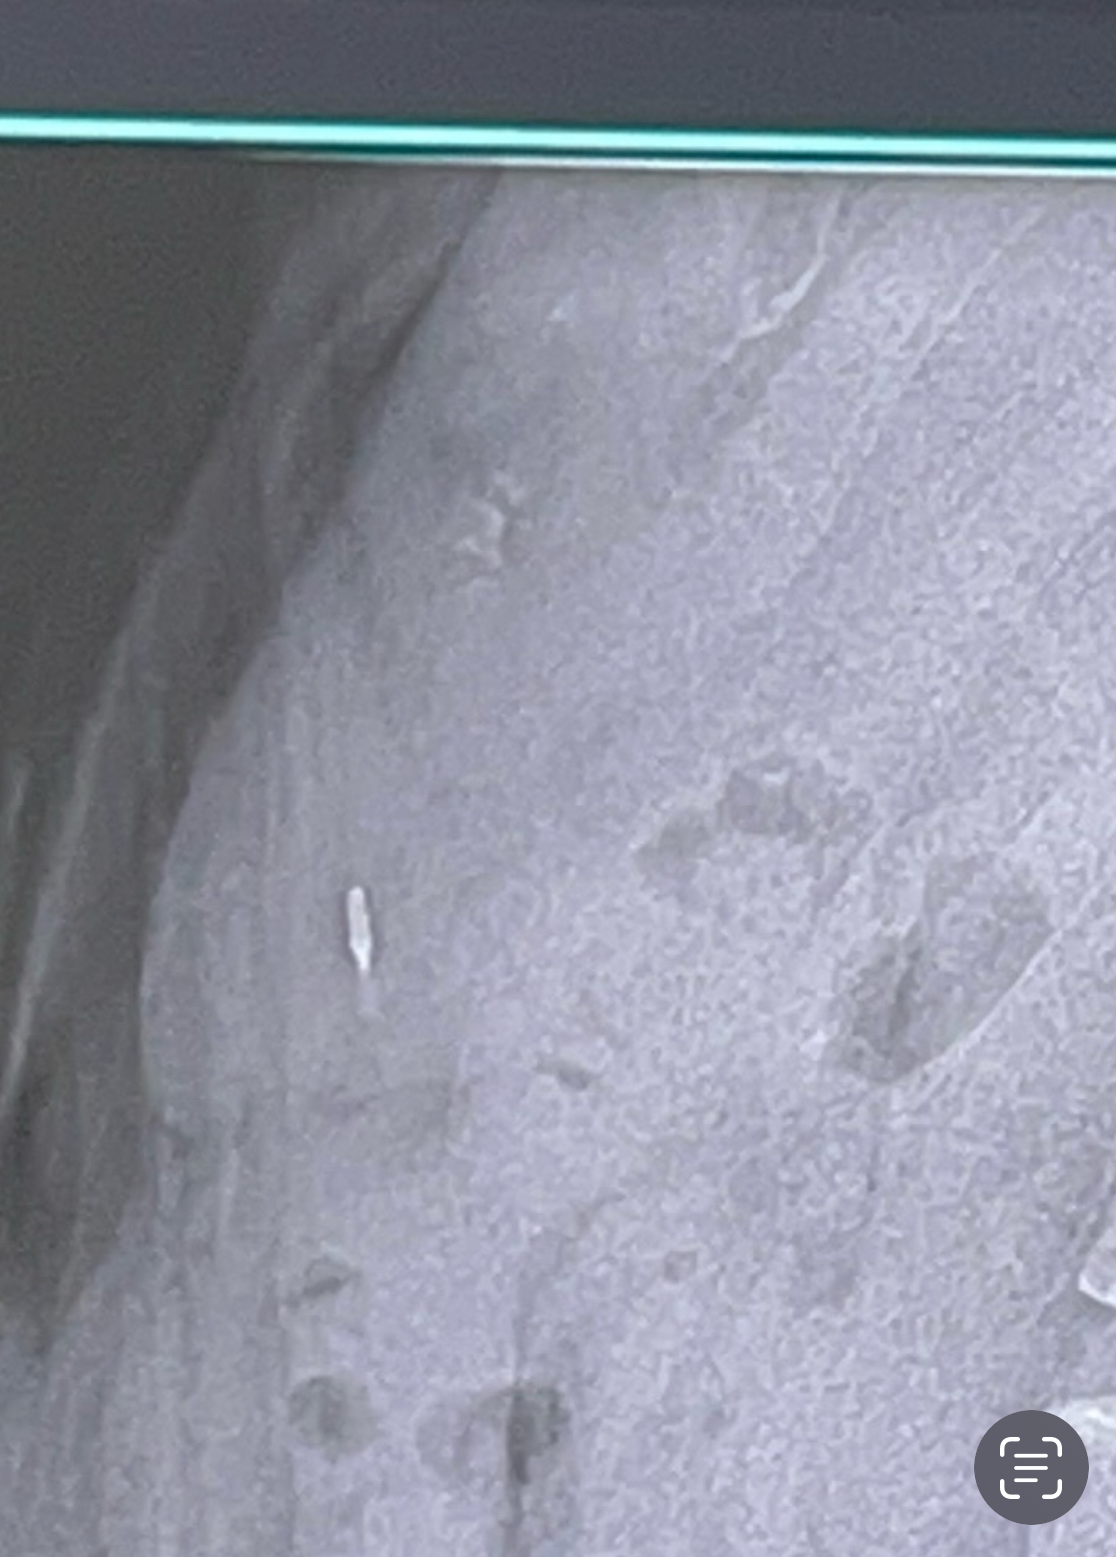

주말에 지인 치과 병원 근무자를 만나서 물어봄

사진 보더니

치과 치료용 파일이나 버

같아 보이기도 하는데

그건 가끔 정말 어쩌다 가끔 삼킬 확률도 있긴 한데

거의 없다고

보통은 삼키면 다 안다고 이야기함.

해외 사례 찾아봄.

하...이렇게 생긴게 몸속에 들어있다는건가?

도대체 저걸 언제 삼켰고 왜 기억이 안나는걸까?

하나는 언제 빠진거지?